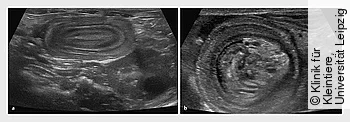

Die starke Entzündung des Darmes durch die Parvovirose führt zu intestinalen Motilitätsstörungen, wodurch eine Invagination entstehen kann. Welpen, die unstillbares Erbrechen und abdominale Dolenz zeigen, sollten sonografisch auf diese Komplikation untersucht werden. In manchen Fällen kann man den invaginierten Darmabschnitt als strangartige Verhärtung bei der Abdomenpalpation fühlen.

Die bildgebende Diagnostik bei Patienten mit Parvovirose dient eher dem Ausschluss anderer Pathologien (z. B. intestinaler Fremdkörper) oder der Erkennung von Komplikationen wie Darminvaginationen.

Ultrasonografische Veränderungen bei Welpen mit Parvovirose sind beschrieben, aber unspezifisch. Dazu gehören z. B. flüssigkeitsgefüllte Darmschlingen, flüssigkeitsgefüllter Magen, Darmatonie und Hinweise auf funktionellen Ileus und verminderte mukosale Dicke in Jejunum und Duodenum.